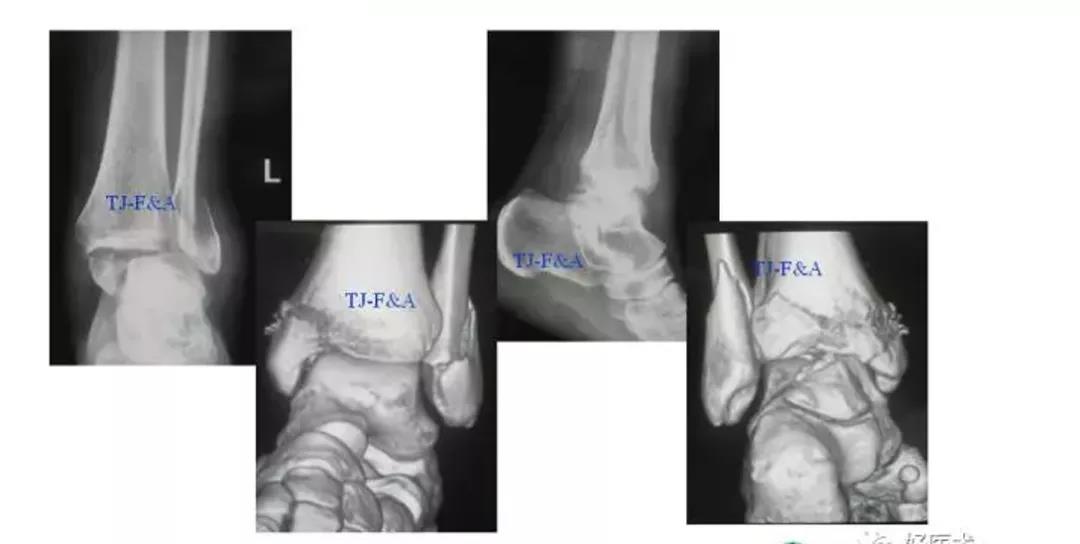

术前DR

术前CT